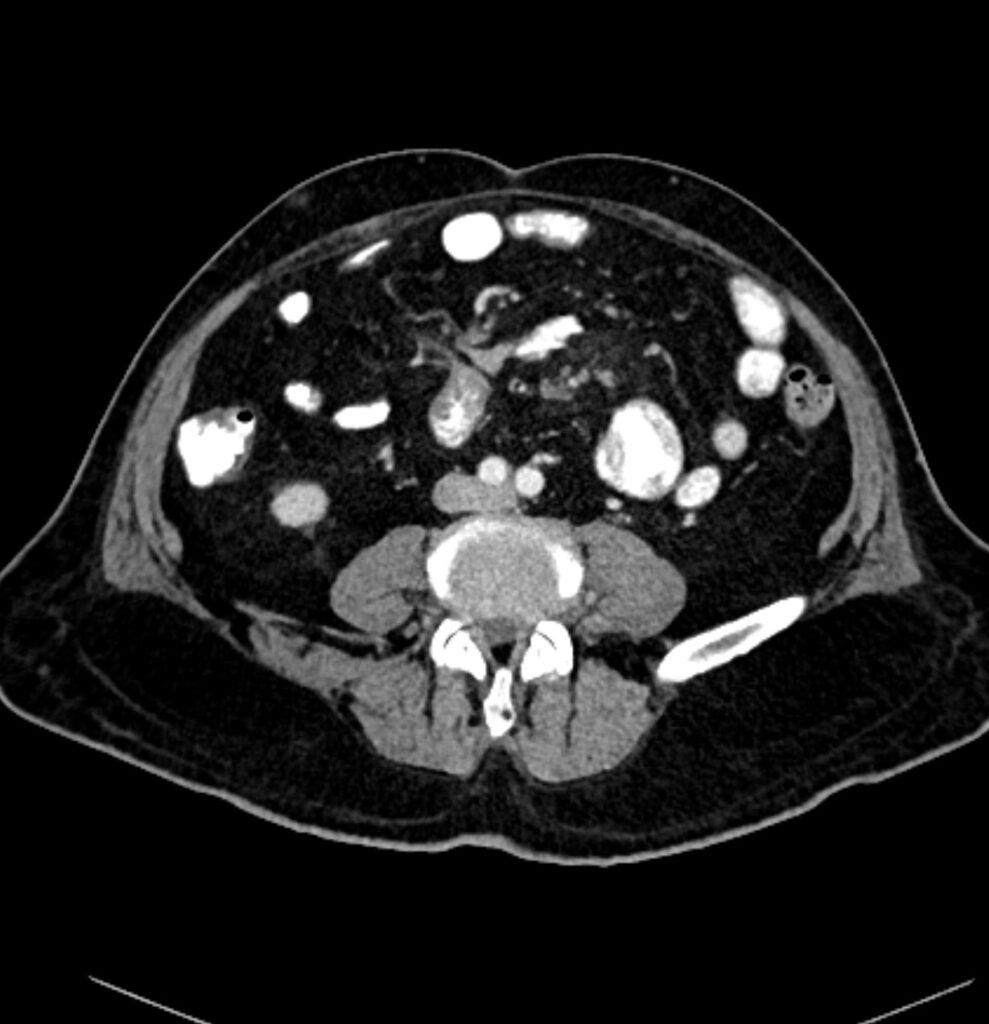

*72-year-old male with abdominal pain and vomiting.

Answer: Small bowel mesentery internal hernia

CT images revealed the dilated loops, mesenteric edema, and beak-like point of obstruction